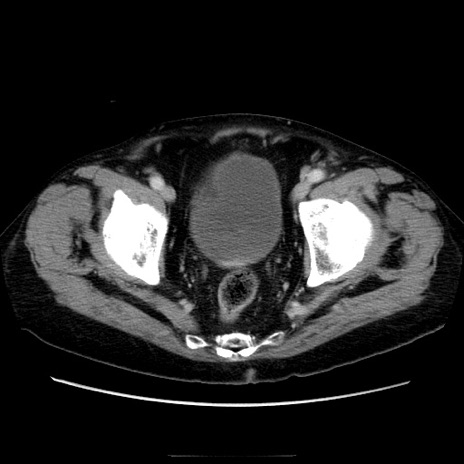

冠状断像

症例21(横断像)

【症例】70歳代男性

【主訴】腹痛

【現病歴】肝硬変・肝細胞癌にてかかりつけの方。約9時間前に食後より腹痛出現。症状が徐々に増悪し、嘔吐出現したため来院。

【既往歴】肝硬変、肝細胞癌(RFA、TACE後)

【身体所見】意識清明、表情苦悶様、BT 36℃、BP 129/78mmHg、P 88bpm、SpO2 97%(RA)、右上腹部から心窩部にかけて圧痛あり、反跳痛なし、筋性防御あり。

【データ】WBC 5800、CRP 0.16